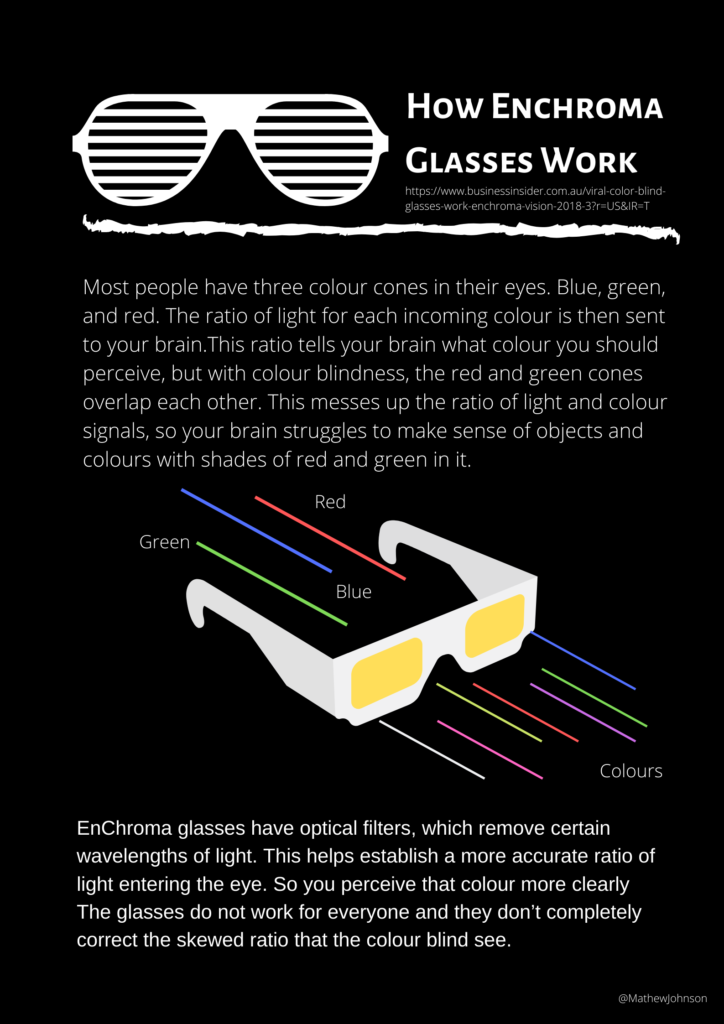

In the retina of your eye, there are two different cell types that detect light. They are referred to as rods and cones. Rods only picks up on light and dark, whereas cone cells are the ones picking up on the colours and are focused towards the centre of one’s vision.

Each person has three types of cones that see colour: red, green and blue. Each cone playing an important part in a person’s overall vision and colour perception. People with typical colour vision can see about 1 to 7 million distinct colours. Those with colour blindness see only about 10% of those colours.

Sadly, a cure for colour deficiency is yet be discovered. Contact lenses and Enchroma glasses with selective filters offer some relief and filter out certain shades to make the world a little easier to see.